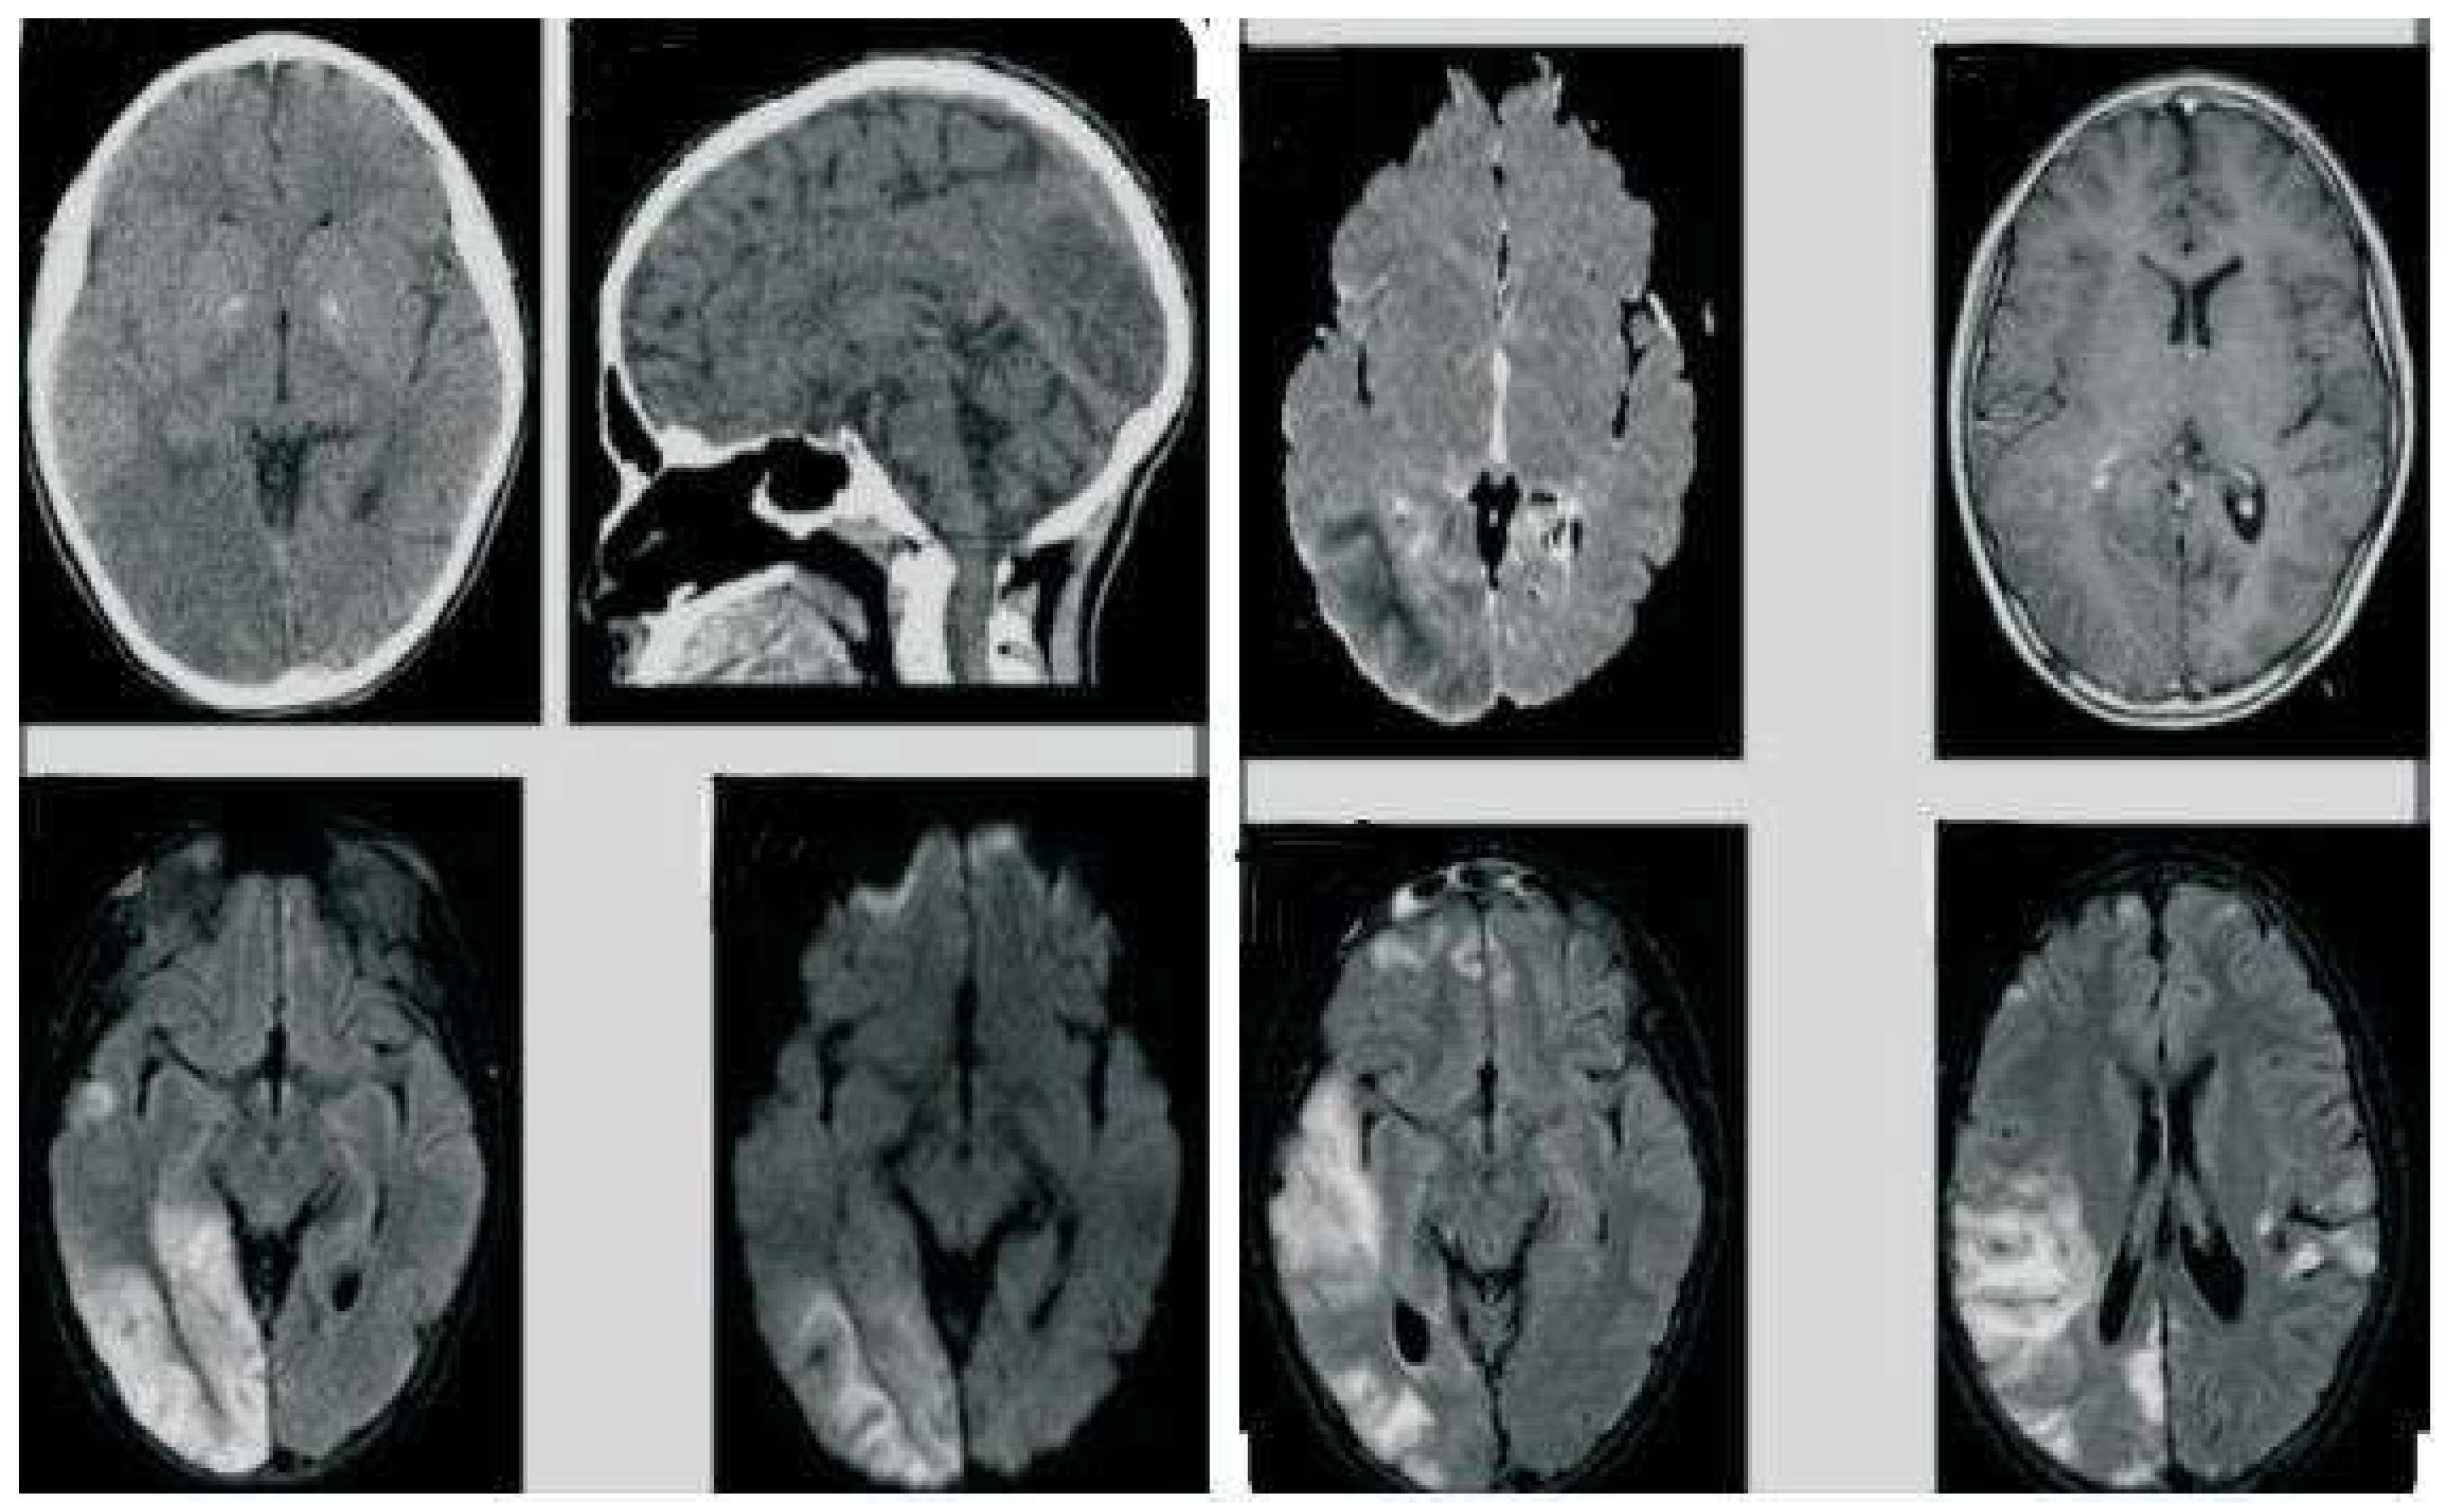

On MRI, Gliosis in right posterior Parieto-occipital lobe with dilatation of occipital horn of right lateral ventricle was noted (Figure 1).

Genetic testing, imaging tests such as magnetic resonance imaging (MRI) scans, and other techniques, tests of blood, urine, and cerebrospinal fluid in addition to muscle biopsy (if necessary) may be used to diagnose MELAS syndrome. Diagnostic workup in our case revealed normal lactate levels in blood but elevated lactate level in cerebrospinal fluid. MRI findings was consistent with mitochondrial dysfunction, and the presence of the m.3243A>G mutation on genetic testing. These findings supported the diagnosis of MELAS.

Figure 1. Gliosis in right posterior Parieto-occipital lobe with dilatation of occipital horn of right lateral ventricle.